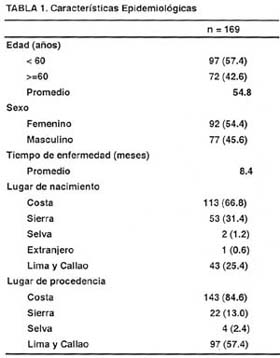

En la Tabla N° 1, se aprecia que el promedio de edad de los pacientes con Linfoma Gástrico es de 54.8 años y la relación del sexo femenino respecto al masculino es de 1.19/1, el tiempo de enfermedad promedio es de 8.4 meses. Respecto al lugar de nacimiento, la mayoría de los pacientes proceden de la costa (66.8%), y de la sierra (31.4%); de la misma manera, respecto al lugar de procedencia, la inmensa mayoría de los pacientes provienen de la costa (84.6%), y en segundo termino de la sierra (13%). Cuando se analiza la procedencia de los pacientes de la costa, Lima y Callao aportan el 57.4% del total de los pacientes, y es evidente que en la presente muestra de 169 pacientes, sólo se objetiva a dos pacientes nacidos en la selva y a cuatro procedentes de la misma.